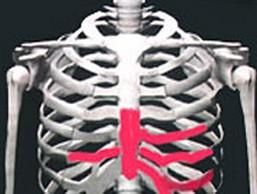

肋軟骨炎肋軟骨炎是指胸肋軟骨與肋骨交界處非炎症性的腫脹疼痛。其原因一般認為與勞損或外傷有關,好發於上臂長期持重的勞動者。臨床表現:好發於20~30女性,男與女之比為1:9。發病有急有緩,急性者可驟然發病,感胸部刺痛,跳痛或酸痛;隱襲者則發病緩慢,在不知不覺中使肋骨與肋軟骨交界處呈弓狀,腫脹、鈍痛,有時放射至肩背部、腋部、頸胸部,有時胸悶憋氣。 一般有西醫治療和中醫治療,中醫治療一般都是舒肋消腫膏。中醫認為肋軟骨炎以氣滯血瘀、瘀血化熱為主,治療則以行氣活血止痛、清熱涼血和營為主。

肋軟骨炎好發於20~30女性,男:女之比為1:9。病變部位多在胸前第2--5肋軟骨處,以第2、3肋軟骨最常見,也可侵犯胸骨柄,鎖骨內側和前下諸肋軟骨。受累肋軟骨處自感胸部鈍痛或銳痛,有壓痛和腫大隆起,深吸氣,咳嗽或活動患側上肢時疼痛加劇、有時向肩部或背部放散。甚至不能舉臂.但局部皮膚無改變;疼痛輕重程度不等,往往遷延不愈,影響病人的工作和學習。疼痛消失後,腫大的肋軟骨甚至可持續數月或數年之久。有時勞累後,疼痛還會發作.發病有急有緩,急性者可驟然發病,感胸部刺痛,跳痛或酸痛;隱襲者則發病緩慢,在不知不覺中使肋骨與肋軟骨交界處呈弓狀,腫脹、鈍痛,有時放射至肩背部、腋部、頸胸部,有時胸悶憋氣,休息或側臥時疼痛緩解,深呼吸、咳嗽、平臥、挺胸與疲勞後則疼痛加重。